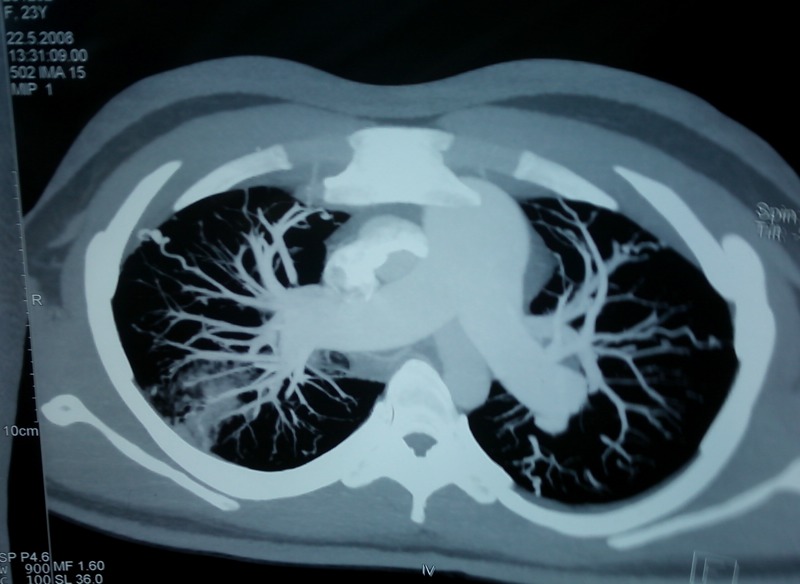

Figure 3.

Contrast CT scan of the chest showing a dilated pulmonary artery due to pulmonary arterial hypertension.

Routine investigations revealed normal haematological, biochemical and coagulation parameters. A chest radiograph showed patchy consolidation in the right upper zone in addition to the features of PAH (figure 1). The sputum Ziehl Neelsen stain was negative for acid-fast bacilli and the tuberculin test was negative. Fibreoptic bronchoscopy showed a normal trachea-bronchial tree. Bronchoalveolar lavage yielded mildly haemorrhagic fluid which was negative for AFB, fungal and malignant cytology. Serological tests for HIV, connective tissue disorders and systemic vasculitis were negative. Two-dimensional echocardiography showed a dilated right ventricle and right atrium and moderate tricuspid regurgitation with moderate PAH (pulmonary artery systolic pressure—67 mm Hg). piral CT angiography showed a dilated main pulmonary artery due to PAH and bilateral numerous pulmonary arteriovenous malformation (PAVM) in the upper and lower lobes with an area of ground glass opacity due to pulmonary haemorrhage in the right lower lobe (figures 2–4). Ultrasonography of the abdomen, gastro-duodenoscopy and MRI brain done did not reveal any other AV malformations. Cardiac catheterisation indicated a mean pulmonary artery pressure of 54 mm Hg (72/40/54 mm Hg) and increased pulmonary vascular resistance (5.6 Wood units), with normal pulmonary capillary pressure (12 mm Hg) and an elevated cardiac index (5.5 l/min/m2). Screening of family members for AVM was negative. Genetic mutation analysis was not performed in this case due to financial constraints.